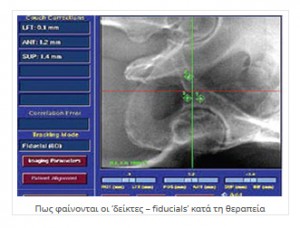

Το CyberKnife® παίρνοντας ειδικές ψηφιακές εικόνες, κάνει έλεγχο της θέσης του ασθενούς και του στόχου και συγκρίνει την παρούσα θέση ασθενούς / στόχου, με την αντίστοιχη θέση που έχει ληφθεί κατά το σχεδιασμό της θεραπείας.

Ο έλεγχος αυτός συνεχίζεται ηλεκτρονικά καθ' όλη τη διάρκεια της θεραπείας. Εάν κάτι μεταβληθεί (π.χ. μετακίνηση του στόχου έστω και δεκάτων του χιλιοστού) λόγω της ύπαρξης των "δεικτών – fiducials" γίνεται αμέσως αντιληπτό από το σύστημα και γίνονται διορθωτικές κινήσεις ώστε η ακρίβεια της στόχευσης να είναι απόλυτη. Ο ρομποτικός βραχίονας κινείται στο χώρο και στέλνει τη δέσμη των ακτίνων που παράγει ο Γραμμικός Επιταχυντής προς το στόχο της θεραπείας με ακρίβεια δεκάτων του χιλιοστού.

Στα παραπάνω έρχεται να προστεθεί και η δυνατότητα παρακολούθησης του όγκου κατά τη διάρκεια της ακτινοβόλησης (real time visualization), διαδικασία η οποία διατηρεί την ακρίβεια της στόχευσης παρά τις μικρές μεταβολές στη θέση του όγκου που προκαλούν οι συσπάσεις του εντέρου.

Προϋπόθεση είναι η τοποθέτηση εντός του προστάτη αδένος, τριών έως τεσσάρων "δεικτών αναφοράς" (3 – 4 fiducials), οι οποίοι εντοπίζονται από το σύστημα κεντροθετήσεως, και ανάλογα με τις μικρομετακινήσεις του στόχου, δίδεται εντολή και ο ρομποτικός βραχίονας διορθώνει την απόκλιση της δέσμης από εκατοστά έως δέκατα του χιλιοστού.

Η τοποθέτηση των "δεικτών αναφοράς" (κομμάτια σύρματος καθαρού χρυσού μήκους πέντε και πάχους 0,8 χιλιοστών (5 Χ 0,8 mm) εμφυτεύονται στον προστάτη με λεπτή βελόνα (18 G) υπό ενδορθική υπερηχογραφική καθοδήγηση.

Οι «δείκτες – fiducials» είναι μικρά κυλινδρικά κομμάτια καθαρού χρυσού (Au 99,9 %) χωρίς ίχνος ακτινοβολίας, μήκους 5 χιλιοστών που εμφυτεύονται μέσα στον προστάτη αδένα όπου θα γίνει και η θεραπεία με CyberKnife®.

Με τον τρόπο αυτό, το ψηφιακό σύστημα αναγνωρίζει τη σωστή θέση του στόχου ανά πάσα στιγμή και σε περίπτωση κινήσεώς του, ο ρομποτικός βραχίονας να κάνει τις ανάλογες διορθώσεις ώστε να υπάρχει πάντα απόλυτη ευστοχία των δεσμών ακτινοβολίας που θα στείλει το σύστημα.

Οι «δείκτες – fiducials» μένουν μέσα στο σώμα για πάντα. Το μικρό τους μέγεθος καθώς και η κατασκευή τους από καθαρό χρυσό τα κάνει τελείως αποδεκτά από τους ιστούς και δεν δημιουργείται καμία παρενέργεια ή αντίδραση. Μάλιστα ο ασθενής μπορεί να υποβληθεί σε οποιαδήποτε εξέταση (Μαγνητική τομογραφία, Σπινθηρογράφημα, Υπερηχογράφημα κλπ) χωρίς πρόβλημα. Όμως στις Ακτινογραφίες της περιοχής, θα εμφανίζονται σαν μικρά μεταλλικά σημάδια, τα οποία εύκολα αναγνωρίζει ο Ακτινοδιαγνωστής και δεν του δημιουργούν διαγνωστικό πρόβλημα.